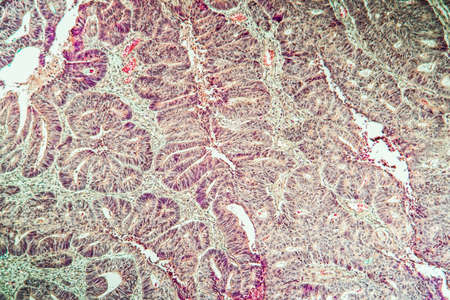

Squamous cell carcinoma diseased tissue under the microscope 100x

Large-bowel adenocarcinoma. Cancer cells arranged in cords or strands with empty central spaces remembering the normal crypts of the colon mucosa.

Differentiated intestinal adenocarcinoma, light micrograph, photo under microscope